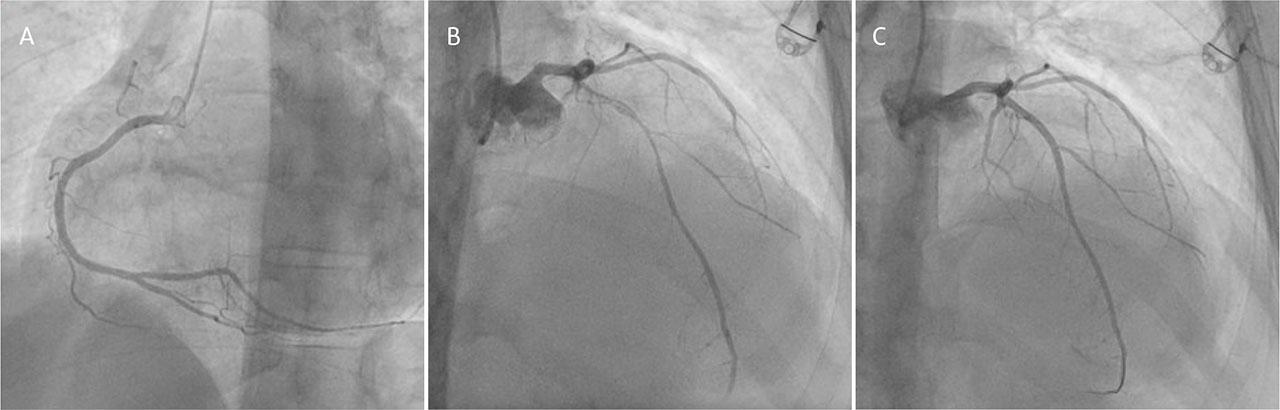

Coronary angiography. A. Right coronary artery. B. Left coronary artery showing subocclusive stenosis in the left anterior descending artery. C. Left coronary artery showing the result of the percutaneous coronary intervention.

To identify the underlying cause of the intracavitary thrombosis, coronary angiography was conducted, which showed a subocclusive stenosis in the left anterior descending artery caused by a partially recanalized thrombus. This lesion was managed with percutaneous angioplasty followed by the placement of a drug-eluting stent. Cardiac optical coherence tomography revealed an extended thrombotic load in segments I/II, involving the origin of the first diagonal branch (D1), with features suggestive of recanalization, preceded by a fibrous plaque without signs of vulnerability. Additionally, after the coronary angiography, antiplatelet therapy with Aspirin 75 mg daily and Clopidogrel 75 mg daily, as well as Rosuvastatin 40 mg daily, was initiated.

In this patient, prompt anticoagulation with unfractionated heparin transitioned to acenocoumarin, alongside comprehensive guideline-directed medical therapy for heart failure, resulted in a significant reduction in thrombus size in 1 month. This underscores the importance of early recognition and management. Moreover, coronary angiography revealed subocclusive stenosis due to a partially recanalized thrombus in the left anterior descendent artery, a very uncommon finding considering the patient's age, which was successfully treated with percutaneous coronary intervention. Coronary imaging, ranging from noninvasive procedures such as coronary CT angiography for risk assessment13 to invasive techniques, has a crucial role even in young patients, as highlighted by the present case.